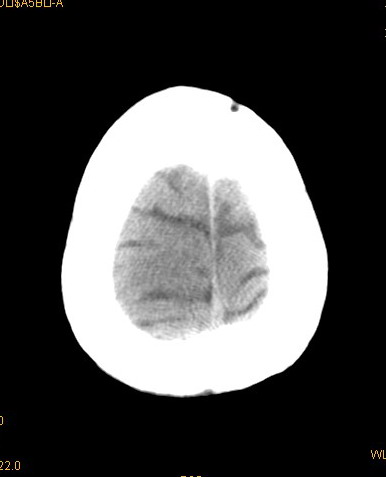

以下是引用卜一在2008-8-14 16:31:00的发言:[br]支持:巨脑回伴脑积水!另:胼胝体发育不良!

以下是引用随光逐影在2008-8-14 16:58:00的发言:[br]胼胝体发育不良;脑积水。

以下是引用同在2008-8-14 19:46:00的发言:[br]巨脑回伴积水,胼胝体发育不良.